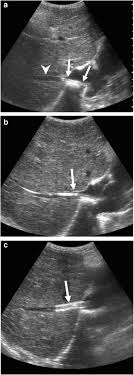

Chiasmata -mə-tə or chiasmas also chiasms 1. Esophageal varices are extremely dilated sub-mucosal veins in the lower third of the esophagus. Located in metro Denver northern Colorado and western Nebraska serving all of the Front Range our team consists of board-certified and fellowship-trained interventional radiologists. This results in hepatic congestion similar to Budd-Chiari syndrome and post-sinusoidal portal hypertension. The patients condition should be monitored throughout the procedure. They are most often a consequence of portal hypertension commonly due to cirrhosis. Toxic injury to liver sinusoids causes sloughing of endothelial cells that embolize to hepatic venules and cause eventual fibrosis of the venules. Coin in the Esophagus. There is no clear consensus regarding the number of occluded veins some authors claim that there should be at least one occluded hepatic vein 7 others state that there are no significant.

Carcinoma of the Colon. Budd-Chiari syndrome a blockage in one or more veins that carry blood from the liver back to the heart. And coumarin skin necrosis adrenal gland hemorrhage and infarction. Toxic injury to liver sinusoids causes sloughing of endothelial cells that embolize to hepatic venules and cause eventual fibrosis of the venules. Chiari malformation CM is a structural defect in the cerebellum characterized by a downward displacement of one or both cerebellar tonsils through the foramen magnum the opening at the base of the skull. Embolism and thrombosis of. La présence dune ou plusieurs affections prothrombotiques est fréquente La prise en charge repose sur un traitement anticoagulant précoce le traitement de l.